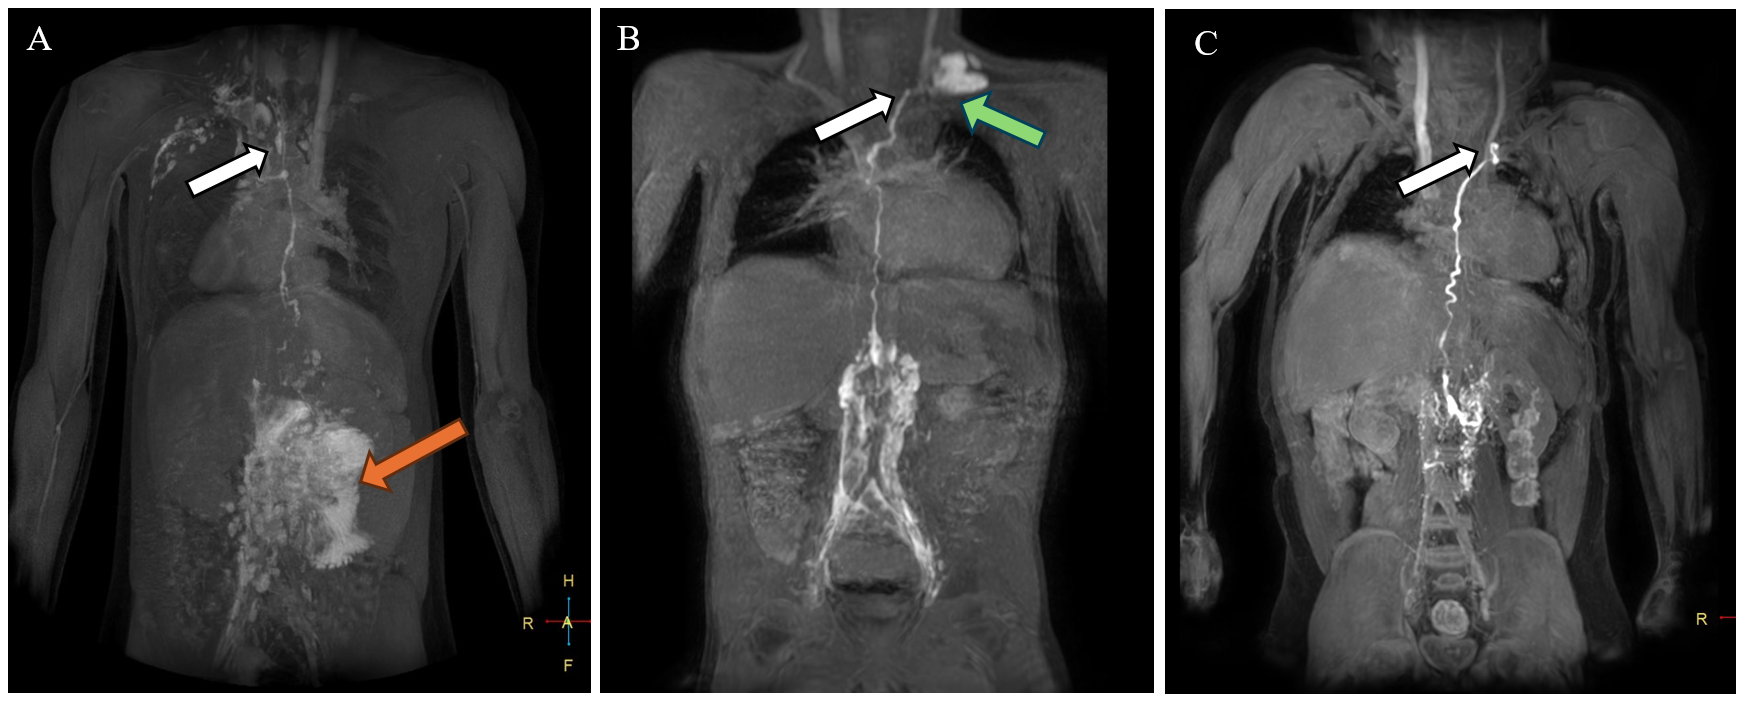

Dori et al. described multiple patterns of lymphatic abnormalities in SV patients using dynamic contrast-enhanced magnetic resonance lymphangiography (MRL).1 It is vital to establish patency and location of the TD. The site of TD drainage may vary in complex anatomical types. In the five Fontan patients described by Alaeddine et al., TD terminated consistently at the jugulo-subclavian venous confluence, although the side of drainage (right vs. left) varied depending on the venous anatomy.4 Figure 2 shows representative images from three Fontan patients who underwent successful surgical turndown at the authors' center.

Figure 2: Results of Preoperative DCMRL for Surgical Planning in Three Fontan Patients With Recurrent PLE

Figure 2

(Panel A) DCMRL on a Fontan patient with heterotaxy syndrome. T1 post–contrast volume MIP acquired 19 min after bilateral inguinal lymph node contrast injection demonstrated marked lymphatic reflux into the mesentery (orange arrow) and an intact TD terminating at the right venous angle (white arrow). (Panel B) T1 postcontrast thick slab MIP acquired 12 min after bilateral inguinal lymph node contrast injection demonstrated lymphangiectasia along the lumbar spine, an intact TD terminating at the left venous angle (white arrow), and lymphatic reflux into the right supraclavicular region (green arrow). (Panel C) T1 postcontrast thick slab MIP acquired 5 min after bilateral inguinal lymph node contrast injection demonstrated an intact normal-appearing TD terminating at the left venous angle (white arrow) without significant lymphangiectasia or lymphatic reflux.

DCMRL = dynamic contrast-enhanced magnetic resonance lymphangiography; MIP = maximum-intensity projection; PLE = protein-losing enteropathy; TD = thoracic duct.